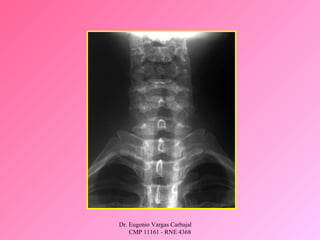

REVISION SECUNDARIA

SE REALIZA UNA REVISION COMPLETA DEL

PACIENTE:

• Historia completa.

• Examen físico completo

1. CABEZA Y CRANEO

2. MAXILO FACIAL

3. CUELLO

4. TORAX

5. ABDOMEN

6. PERINE/RECTO/VAGINA

7. MUSCULO ESQUELETICO/COLUMNA

8. EX. NEUROLOGICO COMPLETO

9. TACTO